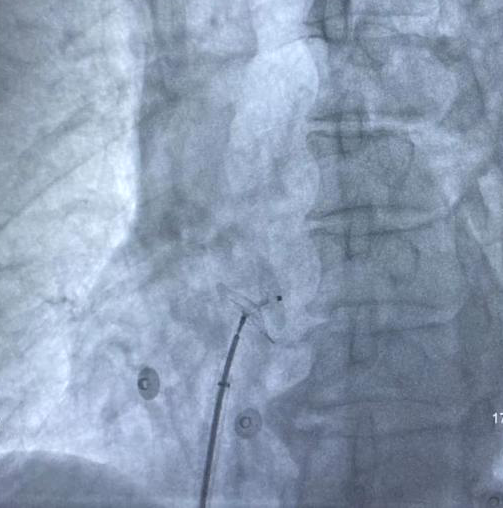

成女士20多年來(lái)飽受疾病困擾,常常無(wú)誘因情況下反復(fù)出現(xiàn)頭痛,且難以緩解,期間經(jīng)過(guò)頭顱CT等相關(guān)檢查未見(jiàn)明顯異常,多次服用止疼藥物效果均較差。成女士的家人找到心血管內(nèi)科王岳松主任團(tuán)隊(duì)尋求進(jìn)一步治療。憑借多年豐富的臨床經(jīng)驗(yàn)、過(guò)硬的專業(yè)技術(shù),王岳松主任判斷患者的頭痛可能是由于卵圓孔未閉所導(dǎo)致。入院后,王岳松主任及董學(xué)濱副主任高度關(guān)注,立即為患者安排心內(nèi)科超聲團(tuán)隊(duì)行右心聲學(xué)造影檢查明確診斷,檢查提示右向左分流II級(jí),同時(shí)患者有反復(fù)頭痛癥狀,具有卵圓孔未閉封堵術(shù)指征。

右心聲學(xué)造影檢查

經(jīng)過(guò)充分的術(shù)前準(zhǔn)備和溝通,以及制定術(shù)中緊急預(yù)案后,心內(nèi)科介入手術(shù)團(tuán)隊(duì)為成某實(shí)施卵圓孔未閉(PFO)介入封堵手術(shù),手術(shù)時(shí)長(zhǎng)不足半小時(shí),術(shù)后患者頭痛明顯緩解。

經(jīng)股靜脈送入封堵傘 封堵傘成功釋放